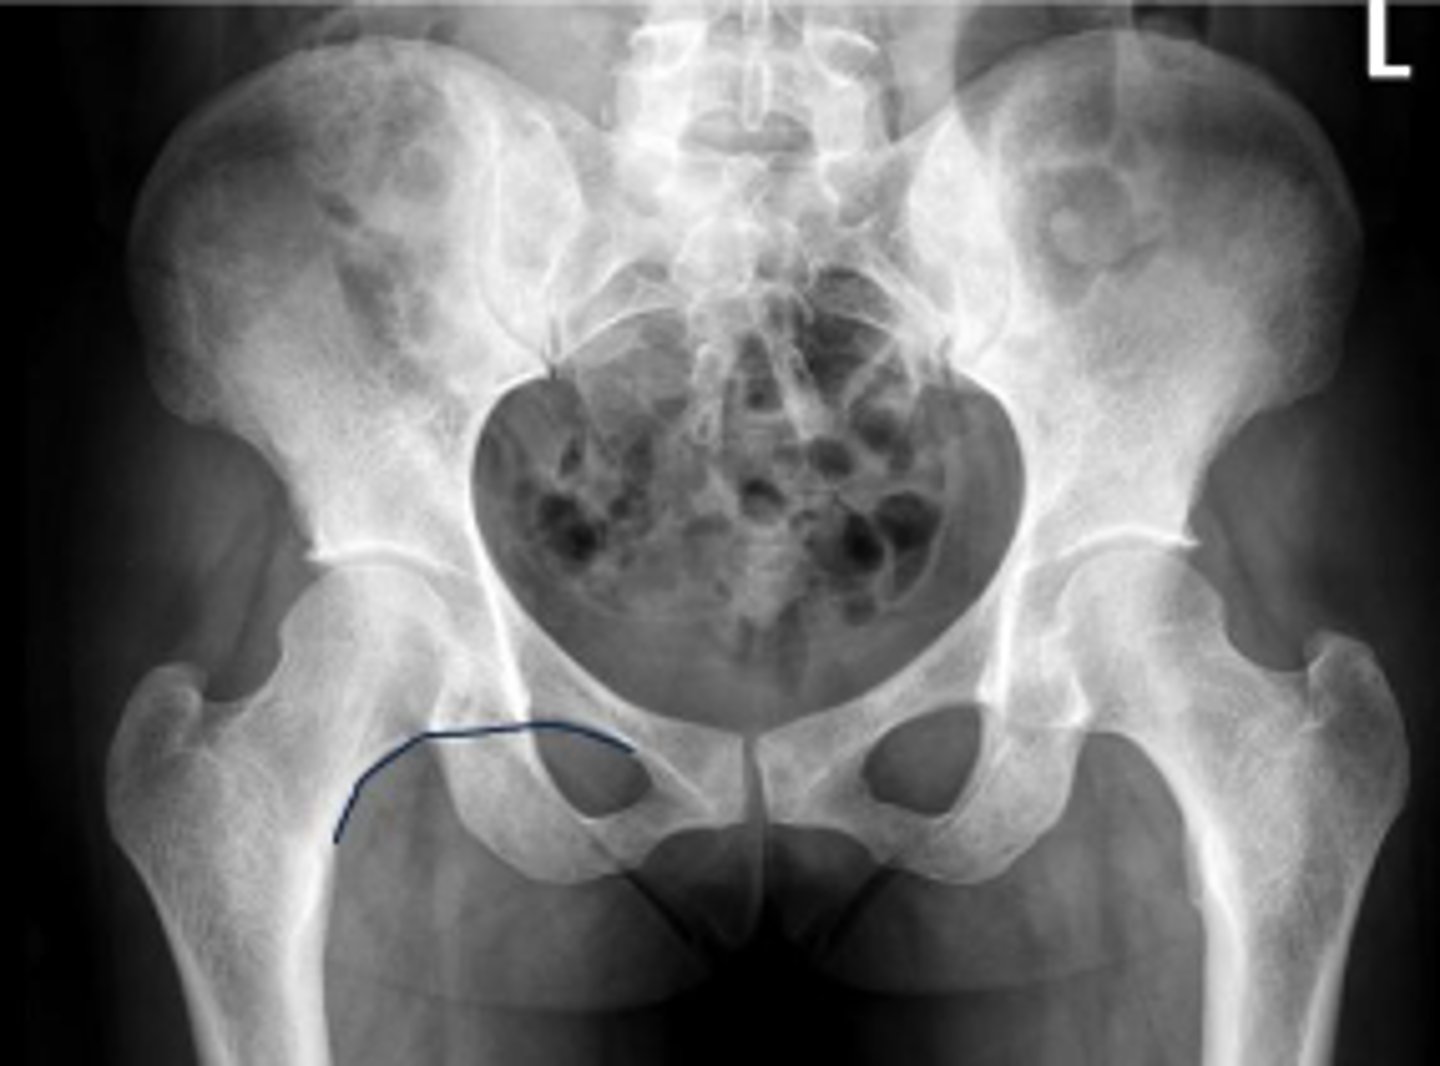

AP pelvis or bilateral hips

What is the name of the radiographic view?

10-15 degrees

How many degrees of internal rotation of the lower extremities is required for this view?

Iliac crest

What are the arrows pointing to?

Sacrum

What is the anatomical structure in between the lines?

ASIS

Left ischial spine

Sigmoid colon

What is outlined?

Right sacroiliac joint

What joint space are the arrows pointing to?

Pubic symphysis

What joint space is the arrow pointing to?

L4/L5 IVD space

Which IVD space is indicated by the arrows?

PSIS

Lesser trochanter of the left femur

Right L5 transverse process

Coccyx

Left obturator foramen

Left superior pubic ramus

Left inferior pubic ramus

AIIS

Soft tissue outline

Right ischial tuberosity

Proximal lateral cortical outline of the diaphysis of the right femur

Right pelvic teardrop

Phleboliths

Greater trochanter of the right femur

Right S3 superior border of the sacral foramen

Greater trochanter of the left femur

L3/L4 IVD space

What IVD space is indicated by the arrows?